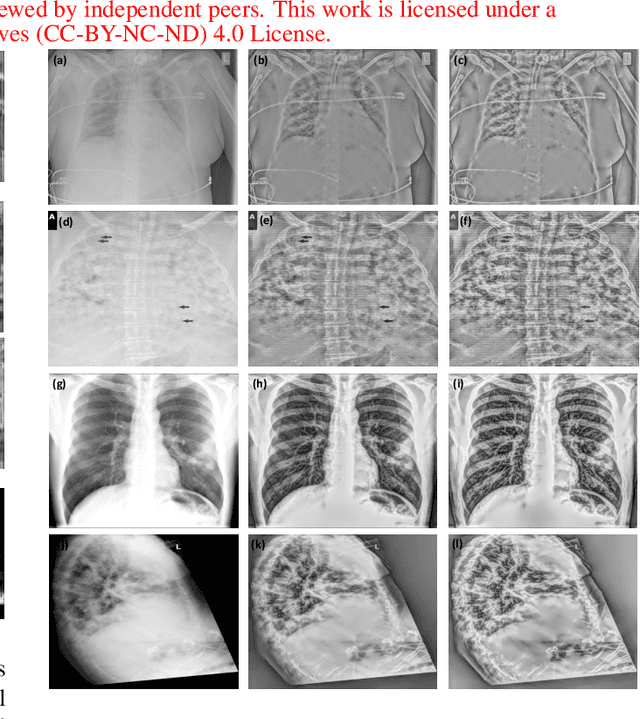

Digital radiography (DR) is becoming popular for the point of care imaging in the recent past. To reduce the radiation exposure, controlled radiation based on as low as reasonably achievable (ALARA) principle is employed and this results in low contrast images. To address this issue, post-processing algorithms such as the Multiscale Image Contrast Amplification (MUSICA) algorithm can be used to enhance the contrast of DR images even with a low radiation dose. In this study, a modification of the MUSICA algorithm is investigated to determine the potential for further contrast improvement specifically for DR images. The conclusion is that combining log compression and its inverse at the appropriate stage with a multi-stage MUSICA and denoising is very promising. The proposed method resulted in an average of 66.5 % increase in the mean contrast-to-noise ratio (CNR) for the test images considered.